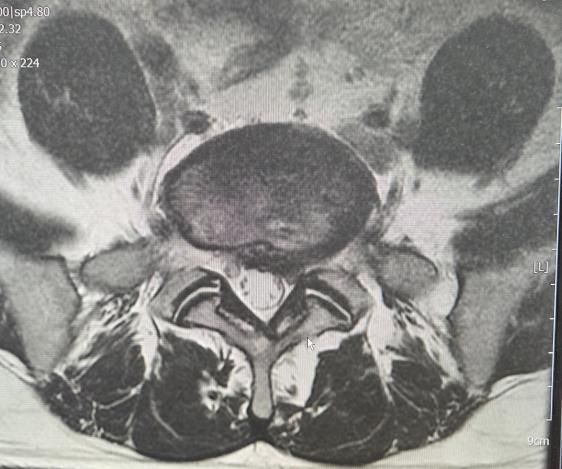

제mri사진 올리겠습니다

• 2번 째 사진

사진을 통해서 보았을 때 L4-L5 디스크도 살짝 탈출증이 있으며, L5-S1 사이의 디스크는 심하게 있어 보입니다. 영상만 두고 보았을 때에는 디스크의 정도가 경미해 보이지는 않지만, 실제로 영상으로 보이는 것과 증상의 정도가 명확하게 상관관계를 가지는 것은 아닙니다. 디스크가 심하게 밀려있고 척추를 누를 수 있긴 하지만, 그럼에도 증상은 심하지 않을 가능성이 존재합니다.